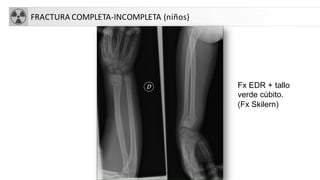

FRACTURA COMPLETA-INCOMPLETA (niños)

Fx EDR + tallo

verde cúbito.

(Fx Skilern)